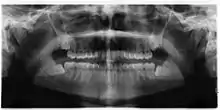

Impacted wisdom teeth are classified by their direction of impaction, their depth compared to the biting surface of adjacent teeth and the amount of the tooth's crown that extends through gum tissue or bone. Impacted wisdom teeth can also be classified by the presence or absence of symptoms and disease. Screening for the presence of wisdom teeth often begins in late adolescence when a partially developed tooth may become impacted. Screening commonly includes a clinical examination as well as x-rays such as panoramic radiographs.

There is no standard to screen for wisdom teeth. It has been suggested, absent evidence to support routinely retaining or removing wisdom teeth, that evaluation with panoramic radiograph, starting between the ages of 16 and 25 be completed every 3 years. Once there is the possibility of the teeth developing disease, then a discussion about the operative risks versus long-term risk of retention with an oral and maxillofacial surgeon or other clinician trained to evaluate wisdom teeth is recommended. These recommendations are based on expert opinion level evidence.[19] Screening at a younger age may be required if the second molars (the "12-year molars") fail to erupt as ectopic positioning of the wisdom teeth can prevent their eruption. Radiographs can be avoided if the majority of the tooth is visible in the mouth.